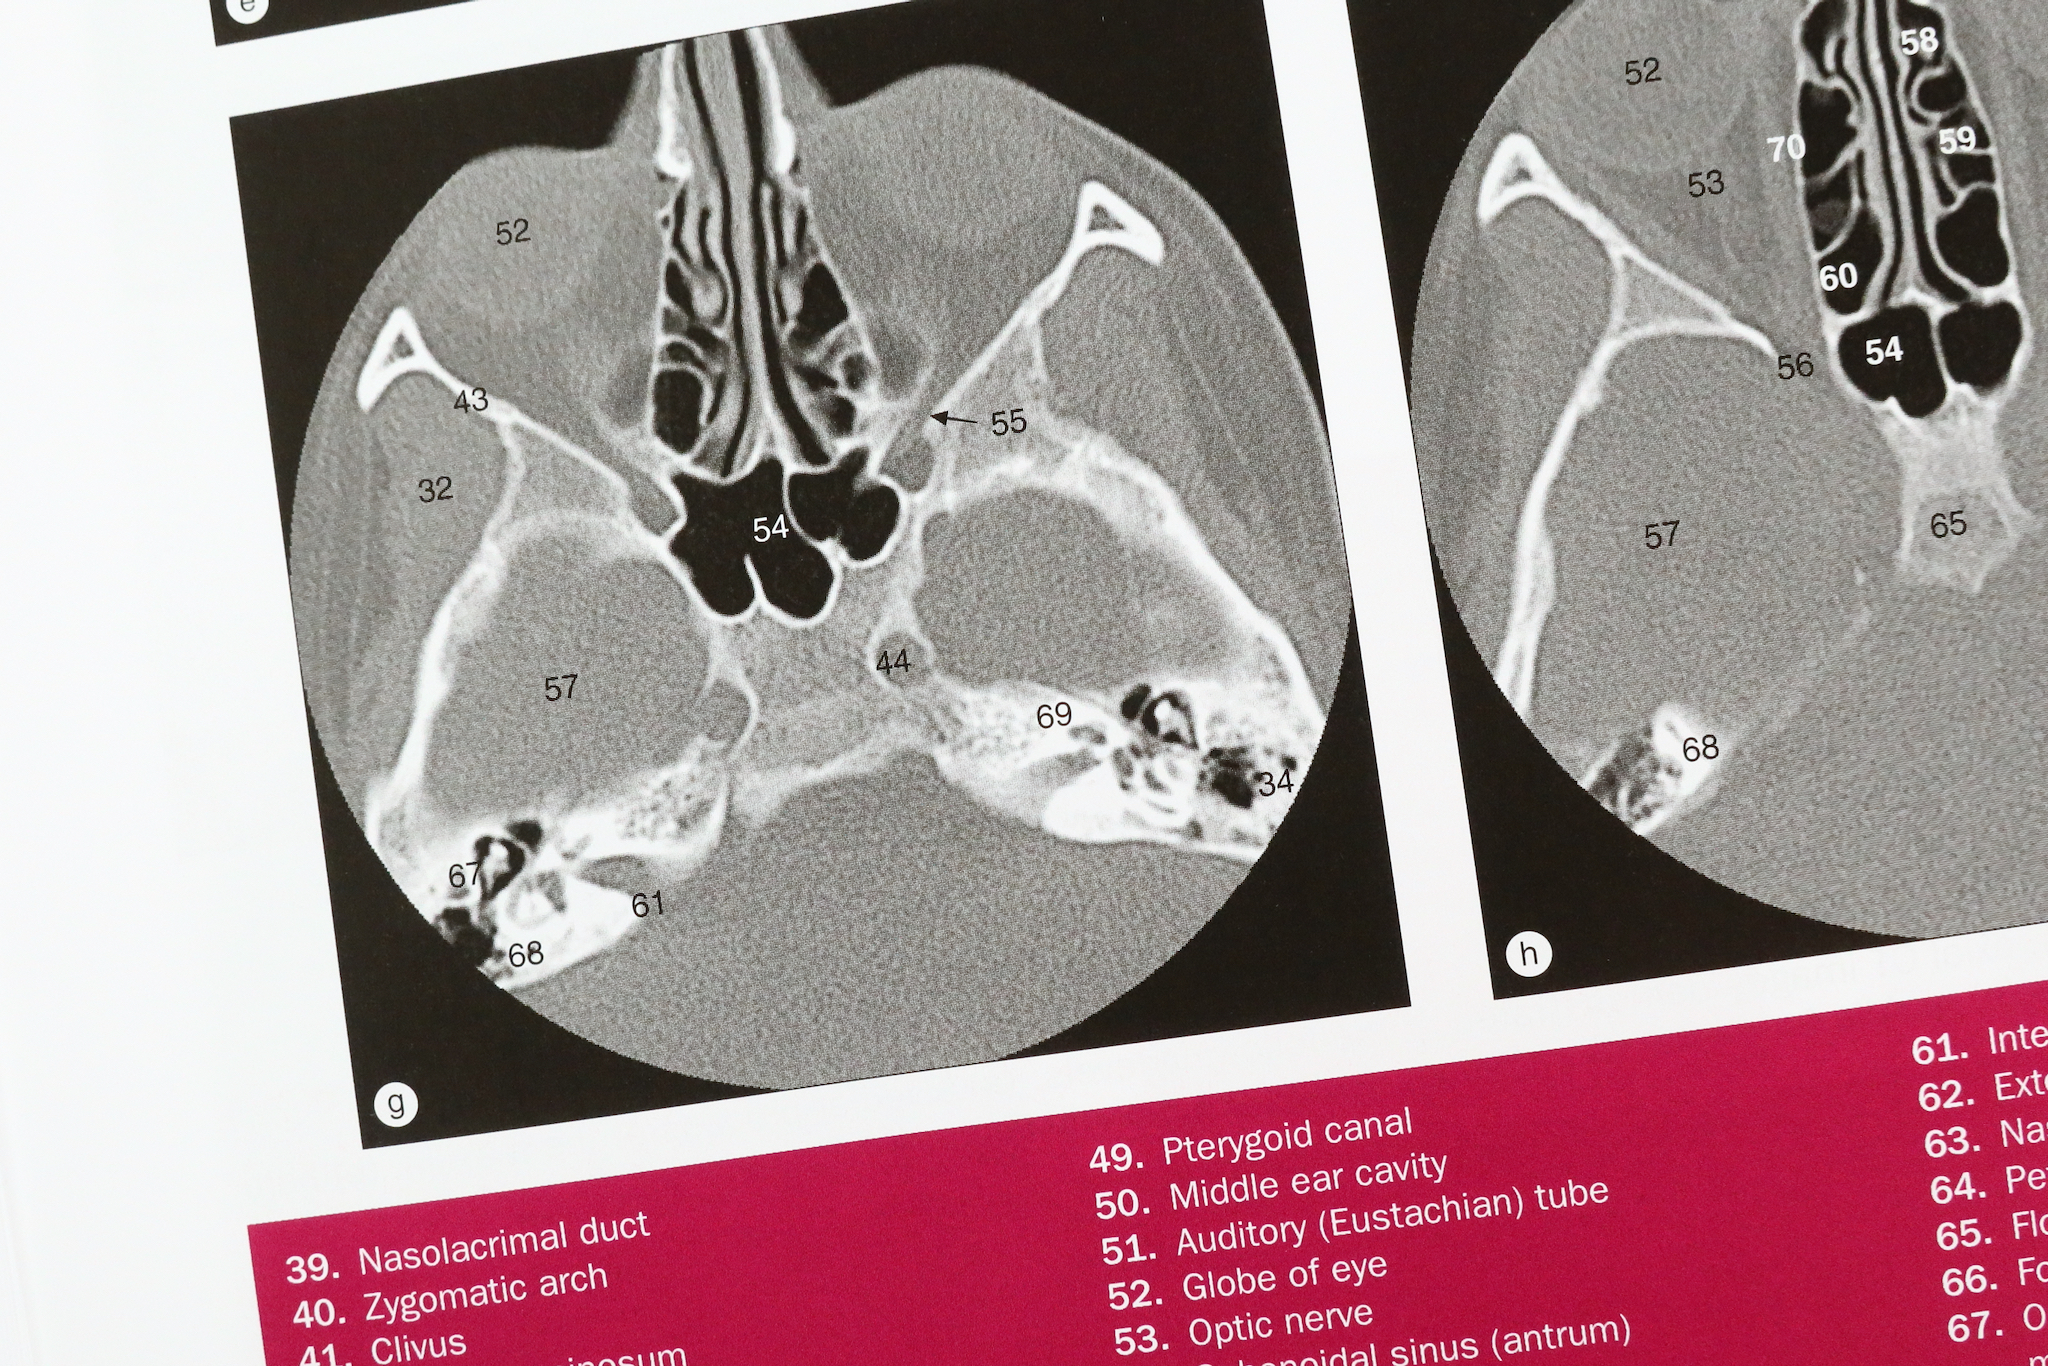

冊子体で胸部の章をみてみよう。単純X線写真、CT、MRI、アンジオグラフィー、ボリュームレンダリングなど、多様なモダリティーの画像を一覧できる。画像上で解剖学的構造が細かく同定されていて、番号で示されている。ひとつの画像に数十のラベルが付いている。大きな判型の見開きを3方向の連続スライスが埋めているのは圧巻だ。

それぞれの画像について、解剖学的構造が細かく同定されていて、ラベルが付されている。系統解剖ごとにラベルが色分けされている。一般には同定の難しい神経にもラベルが入っている。章末に骨格筋の表がついているのが、いかにも整形外科領域らしい。